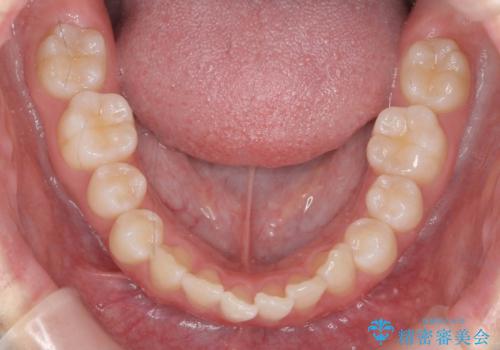

- 前歯が出ていることを主訴に来院。

歯を抜かずにマウスピース矯正をご希望でした。

歯と歯の間をわずかに削り、歯並びを少し横に拡大して並べました。

奥にすき間がなかったため後ろには下げていません。

沢山ひっこめるには4本抜歯でワイヤーの選択肢もありましたが、抜かないでできる範囲をご希望されました。

とがった形の歯列を整えるだけでもだいぶ印象は変わると思います。

今回歯列を広げた結果、上顎犬歯の歯肉は多少退縮しています。